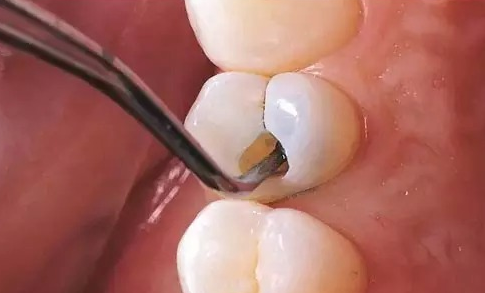

根管治疗的治疗过程是什么样的 牙齿根管治疗术的过程是医生用牙齿根管治疗专用的器械通过彻底去除感染的牙髓以及感染的牙本质和毒性分解产物,严密填塞根管,隔绝细菌进入根管再感染,防止根尖周病变的发... 根管治疗 巨伟懋 510 2023-11-11

什么叫根管治疗 根管治疗的过程是什么样的 根管治疗是牙科常用的一种治疗技术。治疗中,医师使用根管治疗的专用器械,通过彻底去除感染的牙髓以及感染的牙本质和毒性分解产物,严密填塞根管,隔绝细菌进入根管,避免... 根管治疗 范姜英杰 508 2023-10-28